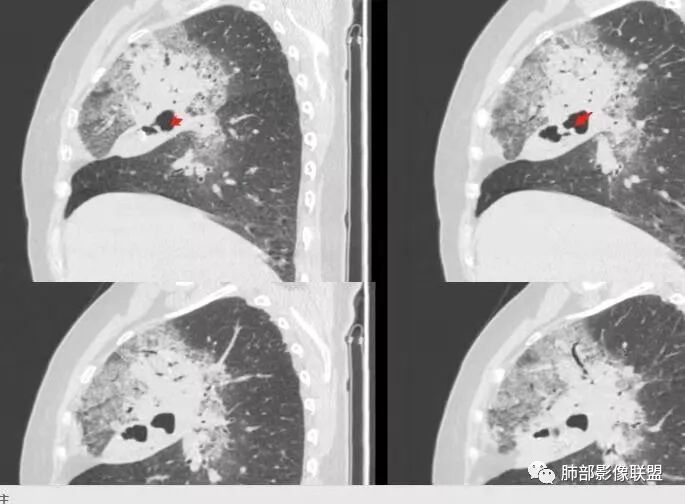

胸CT:右肺上叶实变内可见支气管充气征,近端支气管狭窄,远端扩张,周围可见毛玻璃影,右肺中叶支气管闭塞,并可见气道壁钙化,右肺中叶体积缩小,实变内可见空洞,并可见气液平面,空洞周围可见毛玻璃样影,右肺下叶支气管开口狭窄,右肺门淋巴结肿大。纵隔窗可见病灶与壁层胸膜间隙增宽,考虑良性病变-----感染性病变------TB?

老年女性,慢性病程,咳嗽伴白色粘液痰,无发热腹痛,糖尿病,白细胞及C反应蛋白不高,血沉快,铁蛋白高。胸部CT,右肺上叶大片状实变伴磨玻璃密度影,边界不清,边缘局部膨隆,叶裂弧形下坠,实变影宽基底与胸膜相贴;右肺下叶前基底段见类似病灶;右肺中叶不张并空洞形成,空洞内见气液平面;综合考虑右肺上叶及下叶肺炎型肺癌,右肺中叶结核。

老年女性,病史1月,右肺上中叶大片状影,跨叶,上叶为主,磨玻璃为主,边界模糊,部分实变,内见空洞影和液气平面,壁光滑,支气管开口狭窄,局部有扩张,右肺门淋巴结钙化,首先考虑感染性病变,结核可能,鉴别粘液腺癌。

老年女性,亚急性起病,右肺上中叶大片状影,跨叶,上叶为主,磨玻璃为主,边界模糊,部分实变,内见空洞影和液气平面,壁光滑,洞内可见结节形成,局部有扩张,首先考虑感染性病变,结核可能;洞内可见结节样病灶,鉴别合并曲霉、肿瘤。

患者老年女性,亚急性起病,胸部CT:右肺上叶大片实变,可内见坏死性空洞,可见mGGO,GGO边缘清晰,局部彭隆,内见支气管充气征,可惜没增强,粘液腺癌要考虑,但病灶明显是内朝外不支持,综合考虑结核,建议查痰找抗酸杆菌、气管镜